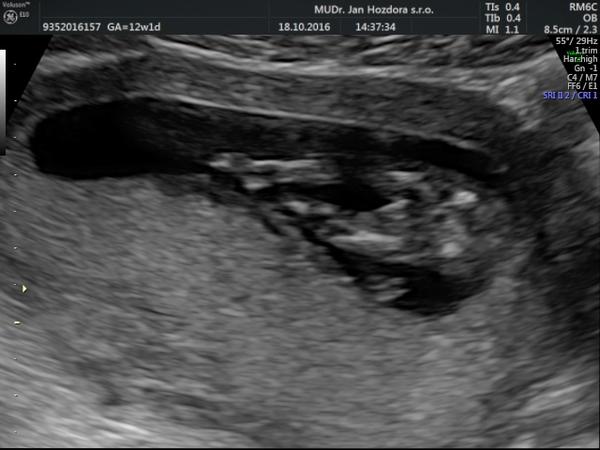

nám na NT screeningu ve 13tt řekl dr., že podle sklonu pohlavního výběžku si je téměř jistý, že je to holčička (u holčiček výběžek směřuje kolmo dolů, u kluků šikmo dopředu). Brala jsem to s rezervou a taky trochu skepticky, měla jsem totiž pocit, že je to kluk. Ve 21tt se holčička potvrdila. Už jsem slyšela víckrát, že dr. poznal pohlaví takto brzo, takže tomu začínám věřit. Myslím, že když je zkušený dr. a má kvalitní UTZ, tak se pohlaví kolem 13tt poznat dá.

Ahoj, já jsem 13+1tt, Na Veveří v Brně mi na screeningu potvrdili na 90% kluka. Pozná se to prý podle pohlavního hrbolku - podle Dr. klukům vrcholek hrbolku míří víc nahoru k bříšku a holky ho mají protáhlejší směrem dolů k nožkám...Uvidíme, co nám potvrdí příště 🙂 ale já věřila, že je to bude kluk už od oné noci 😀 poprosila jsem o něj 😀 a to překvápko, když mi to potvrdili 😀 MUDr. Doubková umí vše krásně vysvětlit, je precizní a velmi příjemná... 😉